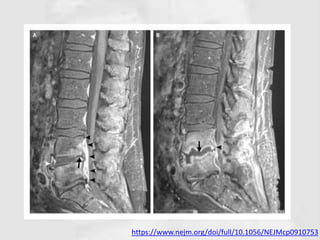

https://www.nejm.org/doi/full/10.1056/NEJMcp0910753

• MRI may show characteristic changes in the

– Vertebral end-plates, intervertebral disc and

paravertebral tissues;

– This investigation is highly sensitive but not specific.

– Similar features may be seen in discitis.